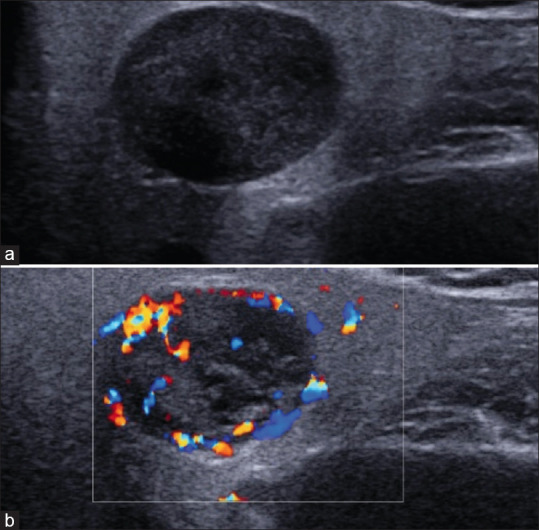

Knowledge of the color Doppler ultrasound (US) characteristics of parotid malignant mucoepidermoid carcinoma and benign basal cell adenoma remains limited. To enhance understanding of these two diseases, we retrospectively analyzed 9 cases of surgically and histopathologically confirmed mucoepidermoid carcinomas and 18 cases of basal cell adenomas. The results revealed that mucoepidermoid carcinomas exhibited irregular and deeply lobulated shapes in 55.5% of cases, ambiguous margins in 88.8%, and punctuate calcifications in 66.7%. In contrast, basal cell adenomas demonstrated regular and shallowly lobulated shapes in 72.2% of cases, clear margins in 100%, and calcifications in only 5.6%. Significant differences were observed in these characteristics between the two tumor types. Therefore, we conclude that the color Doppler US features closely associated with mucoepidermoid carcinoma include deeply lobulated or irregular shapes, ambiguous margins, and punctate calcifications. Recognizing these characteristics can facilitate the differential diagnosis of the two kinds of tumors.

Abstract Image